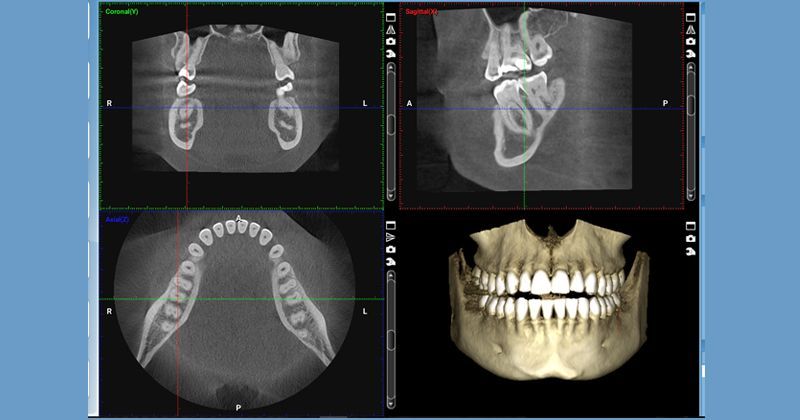

Cone Beam Imaging (CBCT)

Cone Beam imaging gives us a full 3D view of your teeth, jaw, and surrounding structures—all from a single, low‑radiation scan. This technology is essential for diagnosing complex issues, planning dental implants, evaluating wisdom teeth, and more. Because the scan is quick and minimally invasive, it’s especially helpful for patients with dental anxiety or a strong gag reflex. With CBCT, we can plan your treatment with exceptional precision and confidence.